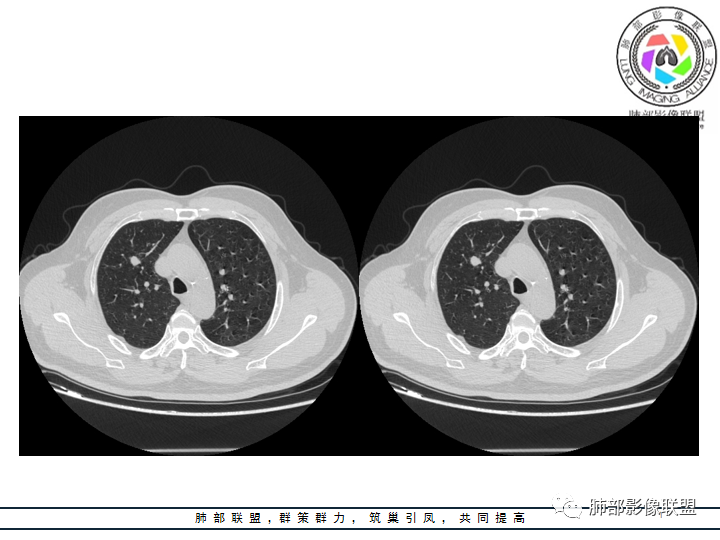

影像资料

老年男性患者,长期吸烟史,没有呼吸系统临床表现。胸部CT示右肺上叶实性密度结节影,密度均匀,未见空洞及钙化,边缘较光整,未见分叶及毛刺。血管影旁现侧出,支气管进入并截断,不均匀强化。

影像上结节影或块影一旦与支气管密切相关(如截断),不支持硬化性肺细胞瘤、错构瘤、孤立性纤维瘤等良性病灶。如此清晰的边缘也不符合一般意义上的炎性渗出。